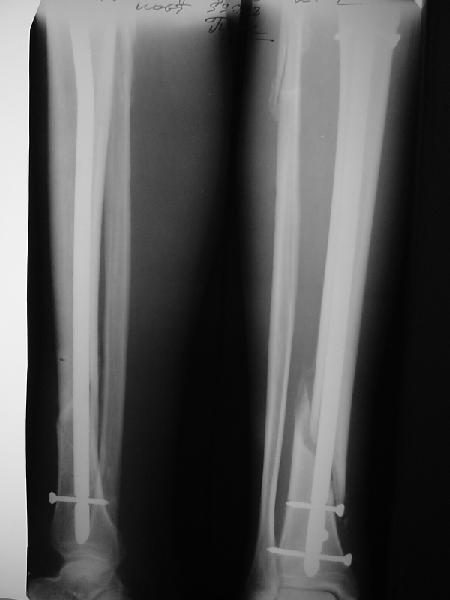

Ok. А также и следующий, в 3 месяца.

Это наглядная демонстрация возможности ранней полной нагрузки при нестабильном по оси повреждении, причем не в самых благоприятных механических условиях - при плохом сопоставлении, со слабым фиксатором.

JOM> Ваш больной имеет счастье, что первым согнулся проксимальный

JOM> замыкающий винт, а не дистальный и гвоздь не пенетрировал

Это не счастье, а тонкий инженерный расчет ;-))

Сверху - один статический винт, а снизу - три. Что раньше сломается? Конечно, он потом и нижние сломал, и Вы правы, если бы верхний динамичесий винт уже уперся бы в нижний край отверстия, будь гвоздь подлинее, перфорировал бы сустав как пить дать.

Как я уже говорил, мы сделали выводы из этого и других подобных случаев. Очевидно, решений проблемы два - либо уменьшить нагрузку, либо увеличить прочность фиксатора. Первое решение работает не со всеми больными, так что пошли по второму пути - мы больше не используем гвозди с запирающими винтами диаметром 4 мм.